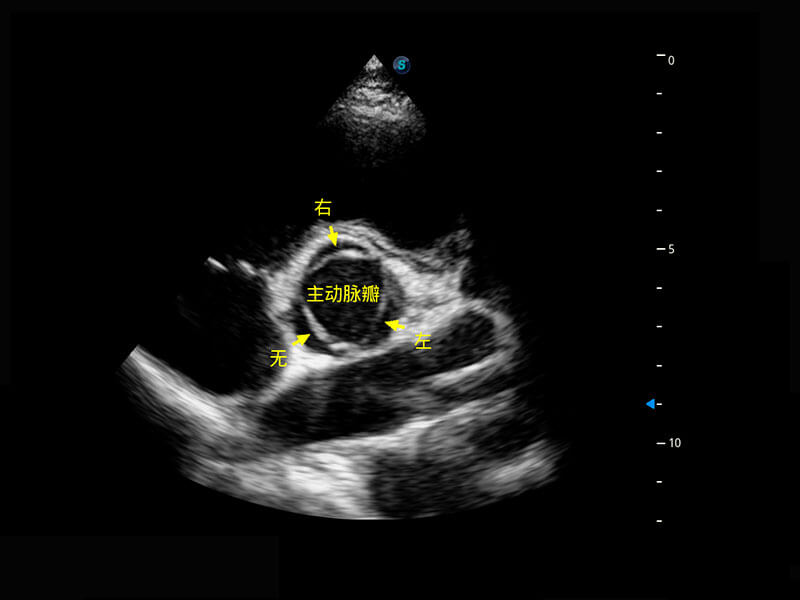

四腔切面

P60搭载一系列胎儿心脏成像技术,实现精细的胎儿心脏评估。